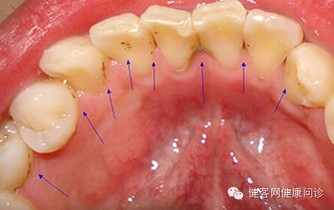

4、自測肝臟功能:看舌頭

把舌頭捲起,通過照鏡子觀察舌底是否出現靜脈曲張。

舌頭靜脈能夠反映肝臟健康,肝門靜脈與上下腔靜脈相通,當肝臟出現問題時,血管狹窄造成肝靜脈擴張,口腔的靜脈也會擴張。

如果舌底血管粗黑,四周呈紫黑色,肝臟很可能出現炎症、肝硬化、肝癌等病況。